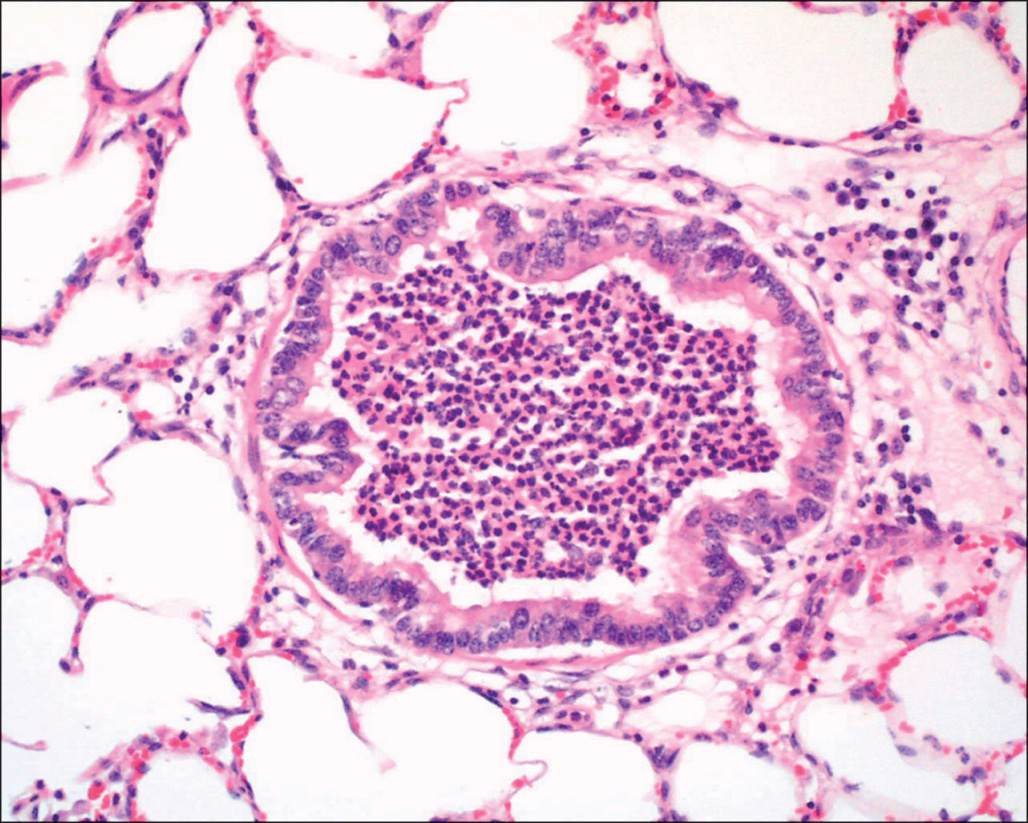

Diffuse alveolar damage affects the pulmonary parenchyma in all lobes, although it is often patchy in distribution, and begins with exudation of protein-rich fluid into alveolar spaces. This proteinaceous exudate is a consequence of damage to and increased permeability of both capillary endothelial lining cells and the epithelial type I cells of the alveolar lining. Within hours the exudates form hyaline membranes, which are a histologic hallmark of this disease process ( Fig. 38.6 ). Within a few days the exudate begins to undergo organization by spindle-shaped fibroblasts within alveolar spaces ( Fig. 38.7 ), and collagenous fibrosis develops, which obliterates alveoli and greatly thickens the septa between alveoli and extends between capillaries and the alveolar surface. Macrophages accumulate within alveoli, and alveolar epithelial type II cells multiply. In the late stages there is severe interstitial fibrosis. There are multiple pathogenic mechanisms involved in this process, and it is not yet clear which of these are most significant in patients with burn injury. , The burn injury itself stimulates activation of complement, which could stimulate vascular leakage in the pulmonary bed. These and many other peptides are thought to activate circulating neutrophils, which produce secondary injury to the vascular and epithelial membranes in the lung. , Conversion of xanthine dehydrogenase to xanthine oxidase in the burn wound can cause release of superoxide into the venous circulation, stimulating endothelial injury and oxidative stress in the lung. The neutrophils reacting to the burn wound undergo an oxidative burst, with release of superoxide into the circulation. This process is greatly enhanced if the patient’s course is complicated by ischemic injury to muscle compartments, limbs, or other organs. Lipid peroxidation is a recognized consequence of burn injury. Superoxide can also react with nitric oxide, produced in the wound or the lung, to form peroxynitrite, a highly toxic substance. Thrombin peptides, released during thrombosis of blood vessels in the wound, can also activate neutrophils and stimulate endothelial cells to express adhesion molecules. The kinin system can be activated during thermal injury, with its systemic consequences. When patients develop sepsis, additional pulmonary damage may be produced by release of proinflammatory cytokines and augmentation of the processes that lead to inflammatory injury of the lung. , Neuropeptides, including substance P and calcitonin gene-related peptide, may have a role in increasing vascular leakage in the airways. Finally, the presence of oxygen in high concentration can itself lead to injury manifested as diffuse alveolar damage. Despite this plethora of mechanisms that can lead to pulmonary injury in burn patients, many patients with massive burn injury do not develop clinically apparent respiratory difficulty. The conditions that seem to be most strongly associated with this form of pulmonary injury are delayed fluid resuscitation, limb ischemia, and sepsis.

This section of lung tissue shows bright pink, homogeneous hyaline membranes attached to alveolar walls and septa of alveolar ducts. This is from a 2-year-old patient who died 8 days after a large scald burn. This represents the exudative phase of diffuse alveolar damage, which may be seen in the absence of smoke inhalation injury. H&E stain.